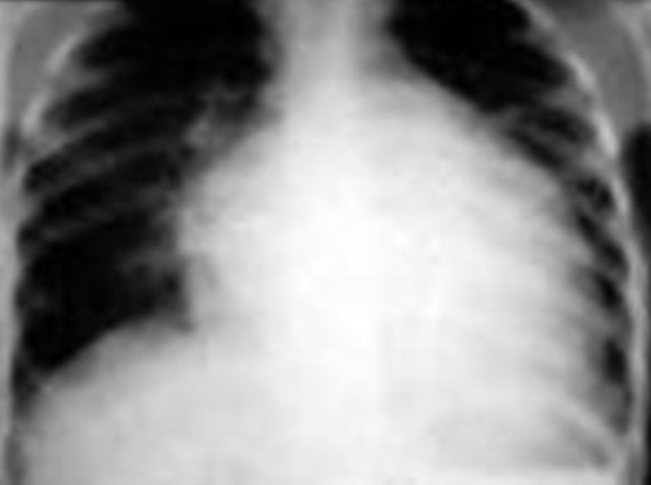

Case: Infant with Poor Weight Gain

- 9-month-old infant with poor weight gain, recurrent chest infection, and cardiac murmur

- Write 2 abnormalities in the X-ray

- Differential diagnosis

- More likely right-left shunt, boot-shaped heart

- TOF if cyanosis